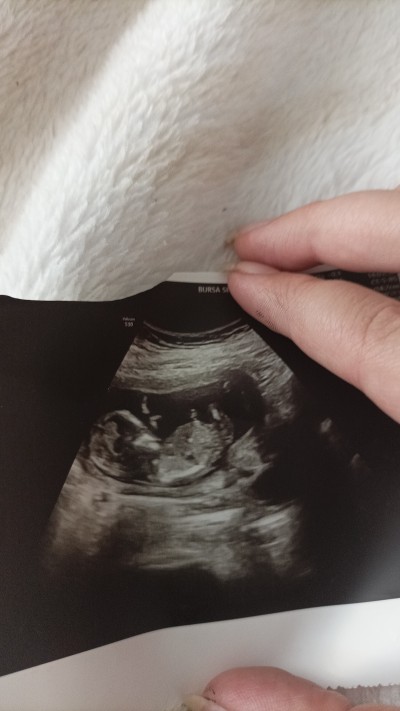

13+4 günlük bir Rabbim hayırlı evlat nasip etsin daha bu tosbiğimin cinsiyeti belli değil sizden tahmin isitiyorum 3 yaşında da kızım var bu arada  ❤️